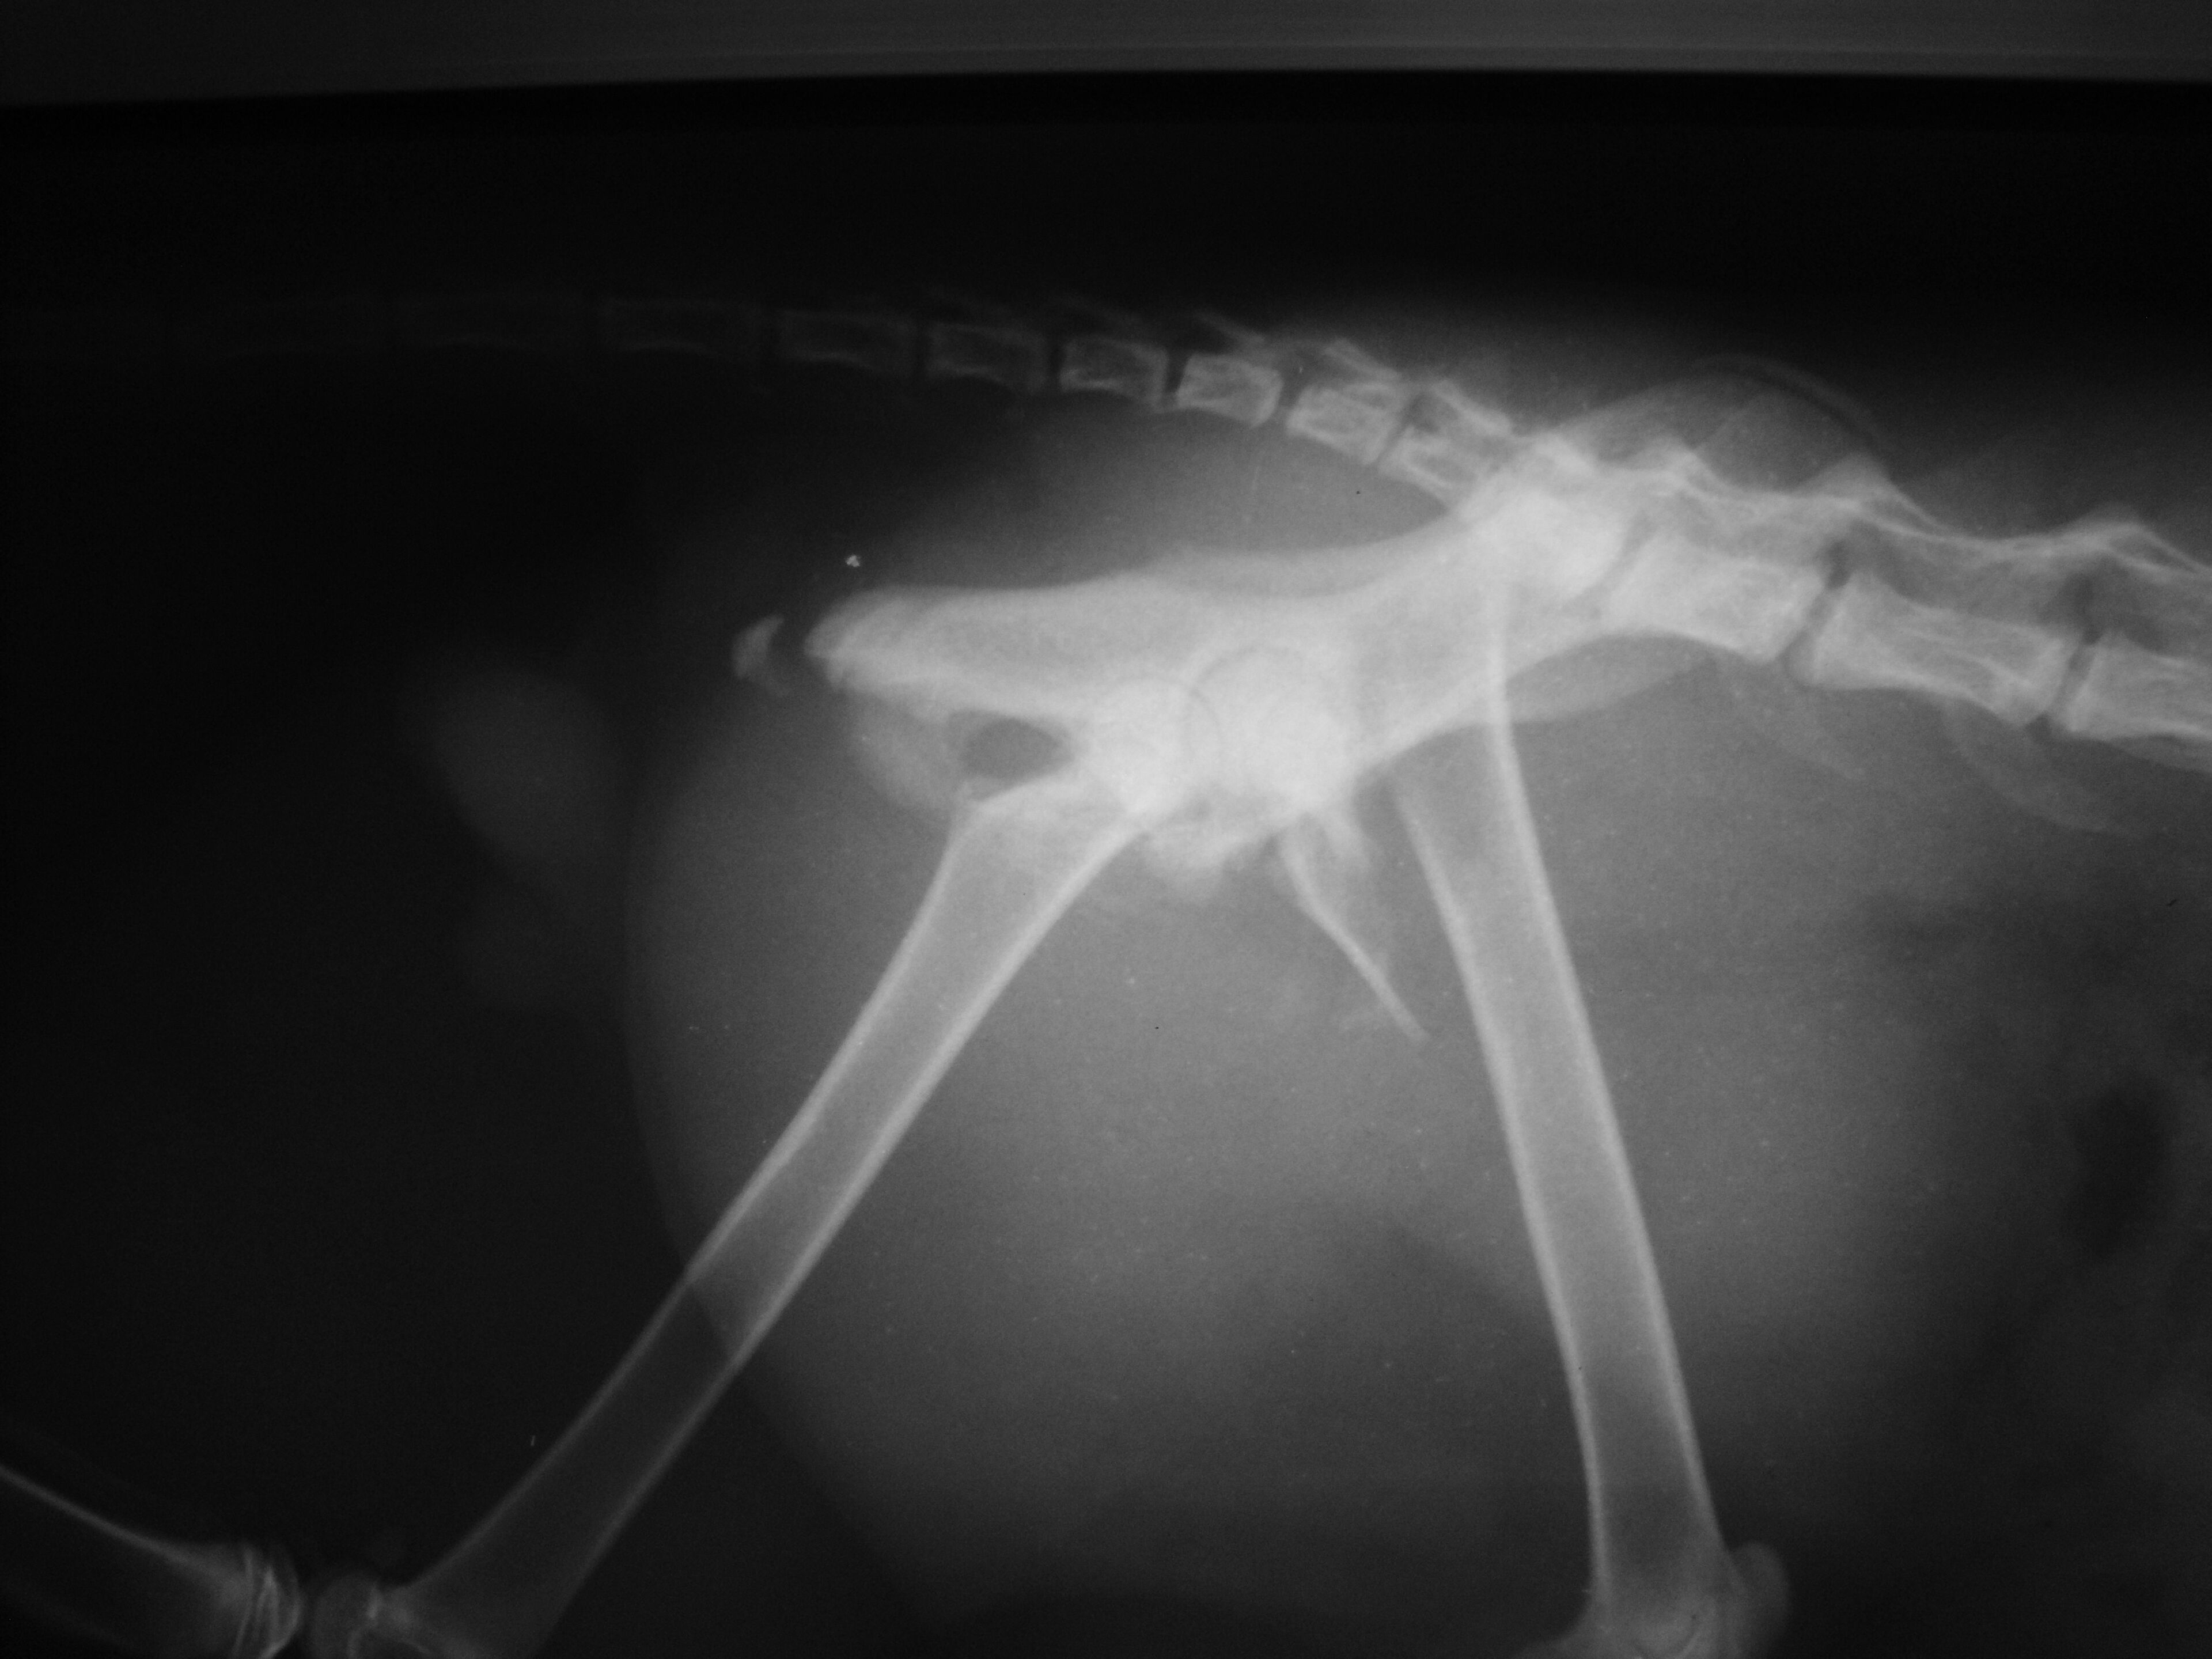

- 編號: 2333

主題: 車禍骨盆骨折 申請者姓名: 呂宜芳 花色: 申請日期: 2013-06-27 10:17:17 申請者部落格: 申請者臉書網址: 所在縣市/合作醫院: 高雄市/樂生動物醫院 治療費用: 17700元 需求人數: 19人 已結案 (2013-08-06 14:16:15) 報名人員: 黑喵喵(已付款)、小飛仔(已付款)、Ed Tsai(已付款)、Annie Liu(已付款)、alicelin x2(已付款)、noahshoes諾達 x2(已付款)、小可愛的媽、Bow Huang x2(已付款)、csaoesc(已付款)、林韋韋(已付款)、謝欣蓓(已付款)、ERic YU(已付款)、Kuen-Lin Tsai(已付款)、閻永安(已付款)、Freesia Tsai(已付款)、張鋅祺(已付款)、布萊梅樂隊(已付款)、 候補人員: 動物病情說明: 喵咪平常在我家附近超市出沒,有時下班我都會去餵他。但有一天附近的阿姨說他被車撞,躲進車子引擎裡,請了消防隊員 花了一番工夫才把他送到醫院。 醫生說他一腳骨折 又 脫臼。需要開刀。 目前他可以走,元氣也好很多了! 只是脫臼的部分還是會使他走路跛跛的。

由於是剛出社會的新鮮人, 負擔不起如此龐大的費用, 希望個位能幫助我和貓咪,目前貓咪已經出院由我照顧中,醫療費用自付一萬元,其餘還請各位幫忙。謝謝!